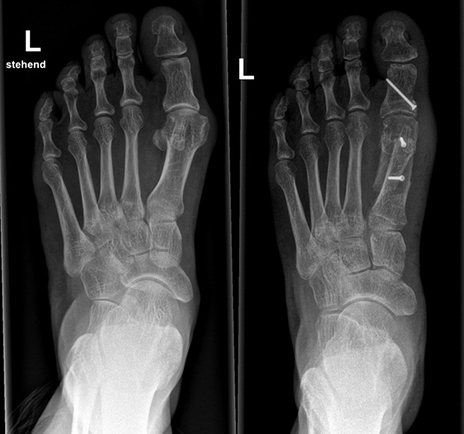

Sehr viel häufiger sind Frauen von der Fehlstellung betroffen. Die Diagnostik der Fehlstellung besteht aus der klinischen und radiologischen Untersuchung, wobei für letzteres in den allermeisten Fällen ein einfaches Röntgenbild im Stehen in zwei Ebenen genug Informationen bietet, um die weitere Therapie zu planen. Es werden hier das Ausmass der Deformität und das Vorhandensein von Arthrose beurteilt.

Vor einer Operation sollten die konservativen, also nicht-operativen Behandlungsoptionen ausgeschöpft werden. Hier insbesondere eine korrekte Schuhauswahl, Einlagen, ggf. Physiotherapie, seltener Schienen. Eine Korrektur der Fehlstellung kann jedoch nur chirurgisch erfolgen und sollte in Betracht gezogen werden, wenn der Leidensdruck trotz konservativer Massnahmen ausgeprägt ist. Die Wahl der Operationstechnik ist abhängig von dem Schweregrad der Deformität und reicht von minimal-invasiven (perkutanen) Korrekturen über offene gelenkerhaltende Verfahren bis hin zu korrigierenden Arthrodesen. Das Ziel der Operation ist die Grosszehe in die korrekte Position zu bringen, Bänder und Sehnen so neu auszurichten und zu straffen und den knöchernen Überstand abzutragen.